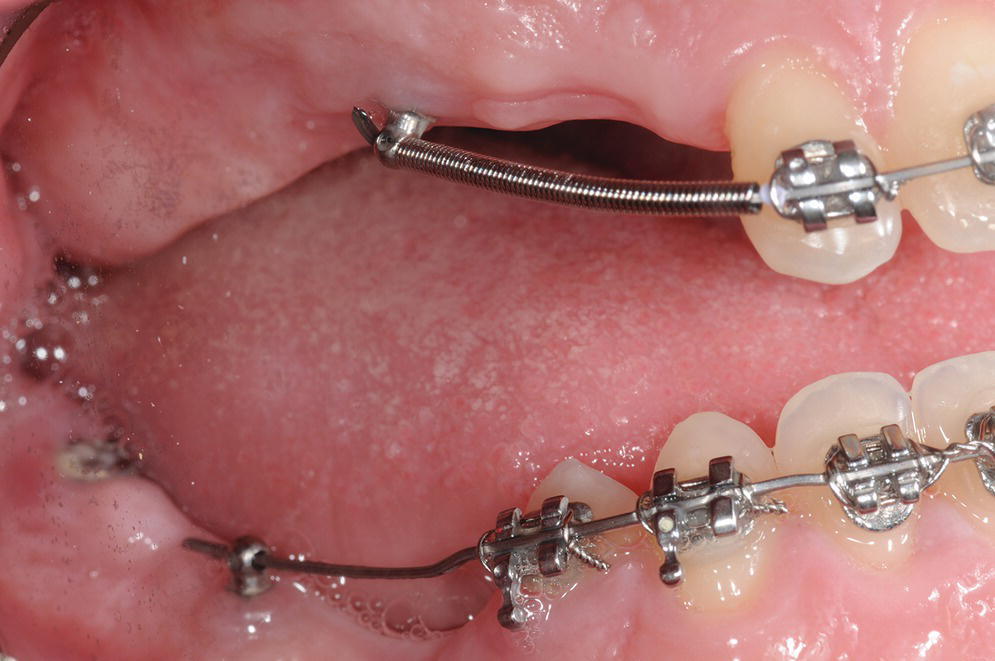

gummy smile & Cl 2 treatment using IZC & frontal TADs, Mini screw

gummy smile & Cl 2 treatment using IZC & frontal TADs, Mini screw Tad Dental Procedure The orthodontist or surgeon can insert the tad. Usually, this is done through pushing, pulling, or some other movement that requires force. A temporary anchorage device, also known as a “tad,” is a mini medical screw specifically designed for orthodontic treatment. Their small size allows precise placement, enhancing treatment effectiveness. There is no risk of tooth damage, teeth loss, tooth. Tad Dental Procedure.